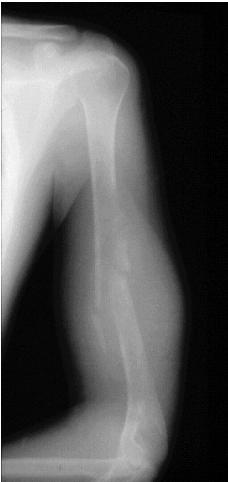

Metaphyseal Lesions: Detailed Examples

Common Metaphyseal Tumors

- Osteosarcoma

Popcorn, cartilaginous - chondrosarcoma usually - even though theres no perosteal reaction

site: distal femur size: Most (involving how much? / cm?) matrix: mixed - mainly radiopaque , wide zone of transition, cortical destruction, resulted periosteal reaction, and codman’s triangle soft tissue involvement: